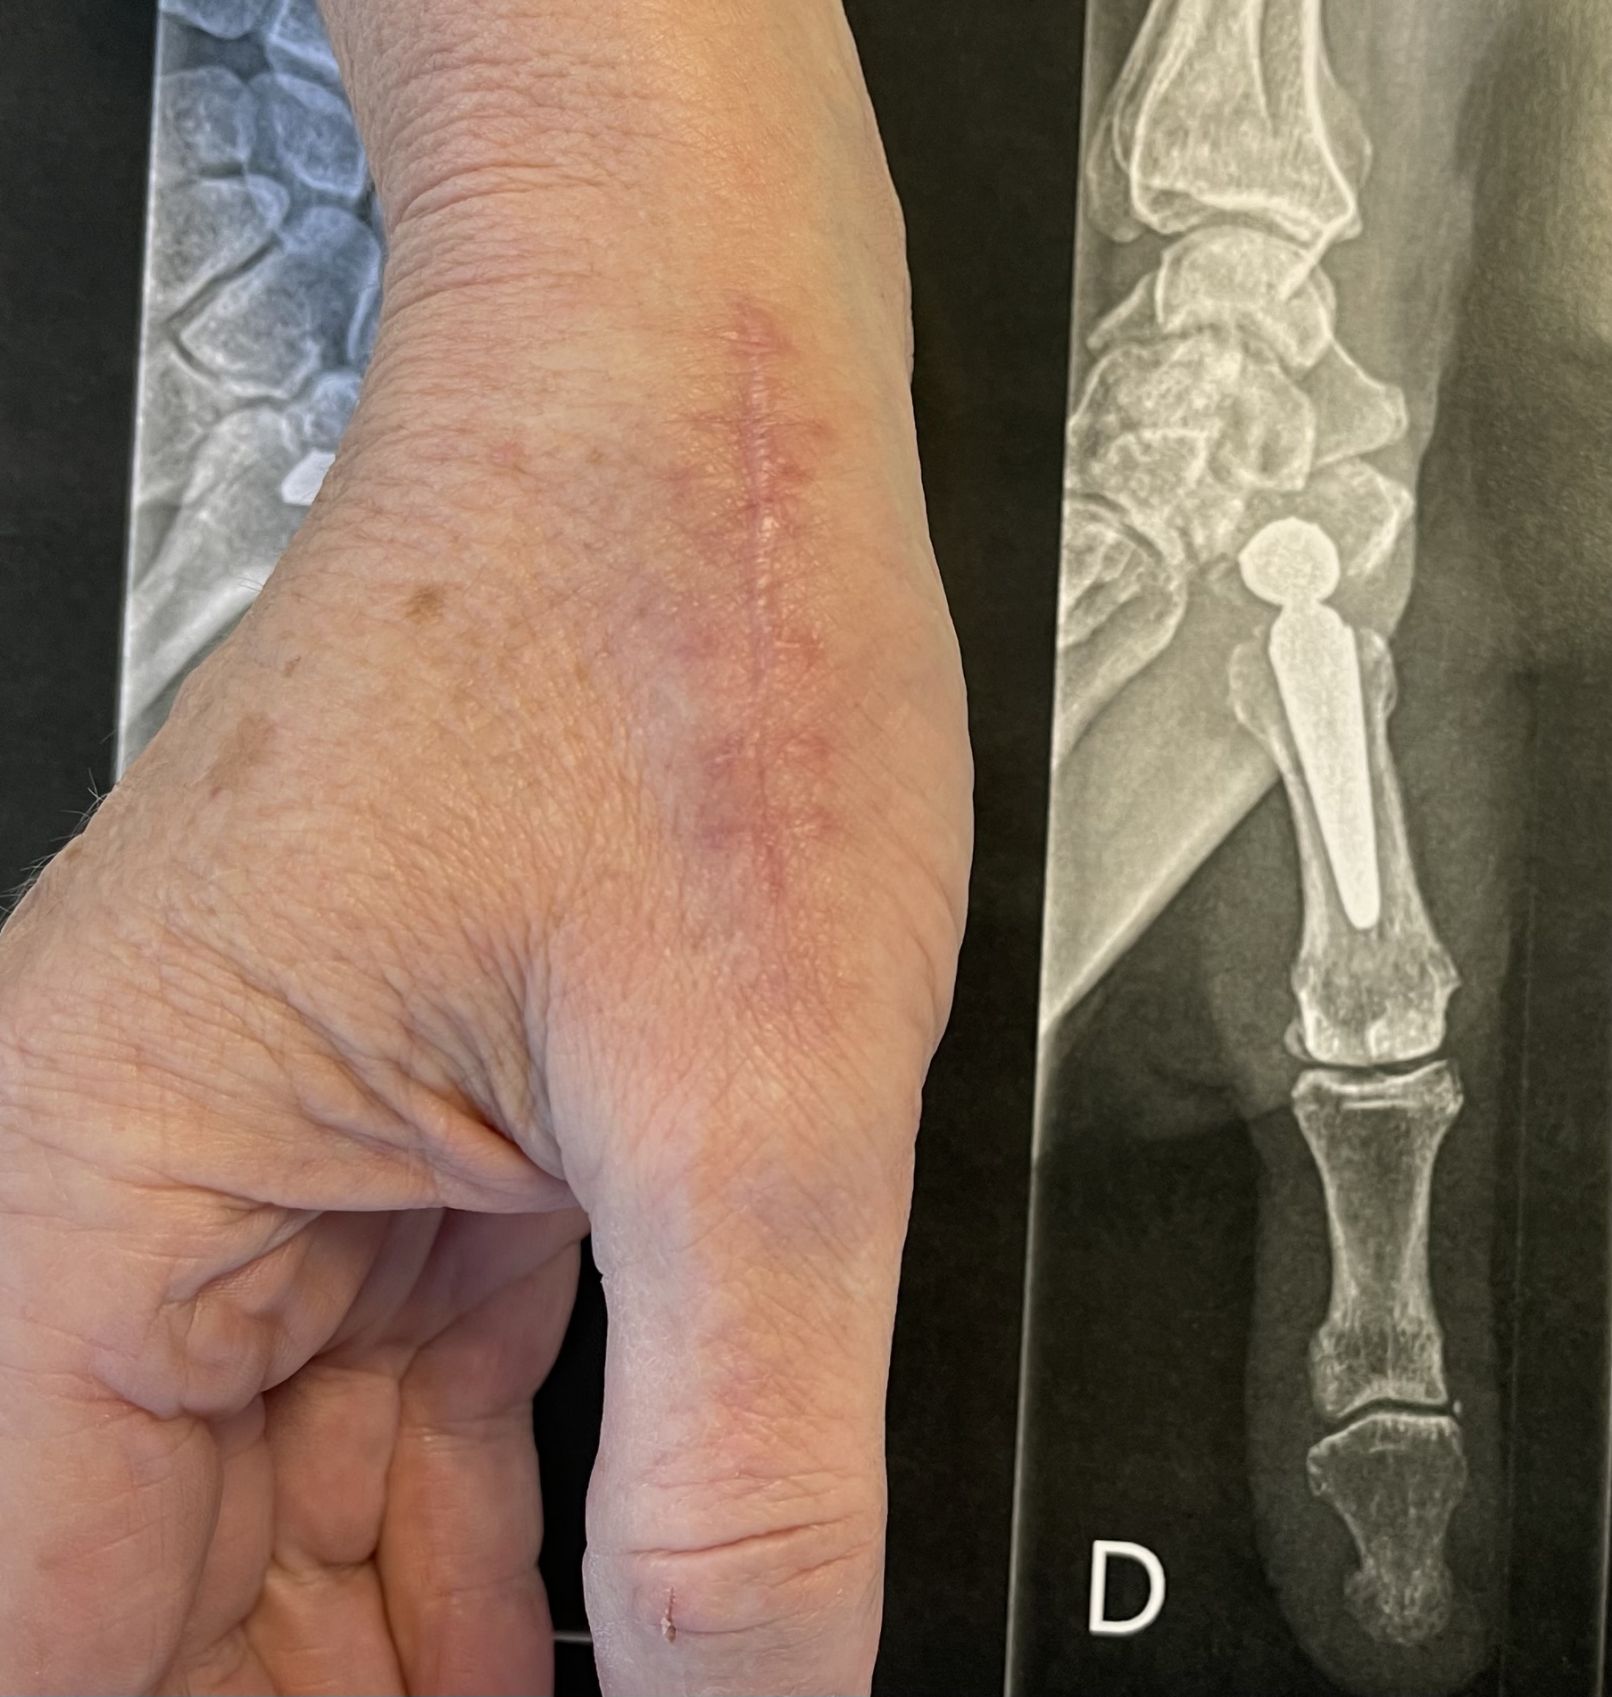

-La prothèse trapezo-métacarpienne : cette prothèse ressemble à une mini-prothèse de hanche, avec une tête sphérique métallique qui s’articule dans une cupule trapézienne en polyéthylène ou en métal. La fixation des pièces prothétiques dans l’os fait appel soit à la régénération osseuse (prothèses non scellées) soit à du ciment (prothèses scellées).

Quelle est l’évolution après le traitement chirurgical ?

Vous sortirez de la clinique le jour même ou le lendemain de l’intervention, avec une attelle maintenant le pouce « écarté » de façon à éviter les douleurs et faciliter la cicatrisation. Un orthèse thermoformée est réalisée au bout de quelques jours si une trapezectomie a été réalisée. Des pansement sont a réaliser pendant 10 à 15 jours.